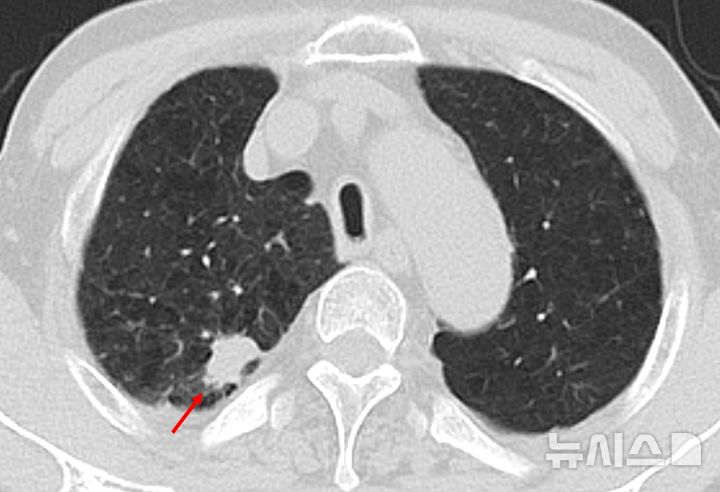

![[서울=뉴시스] 저선량 흉부 CT 검사에서 폐결절 확인 사진. (사진= 한림대동탄성심병원 제공)](https://img1.newsis.com/2025/08/20/NISI20250820_0001922461_web.jpg?rnd=20250820140953)

[서울=뉴시스] 저선량 흉부 CT 검사에서 폐결절 확인 사진. (사진= 한림대동탄성심병원 제공)